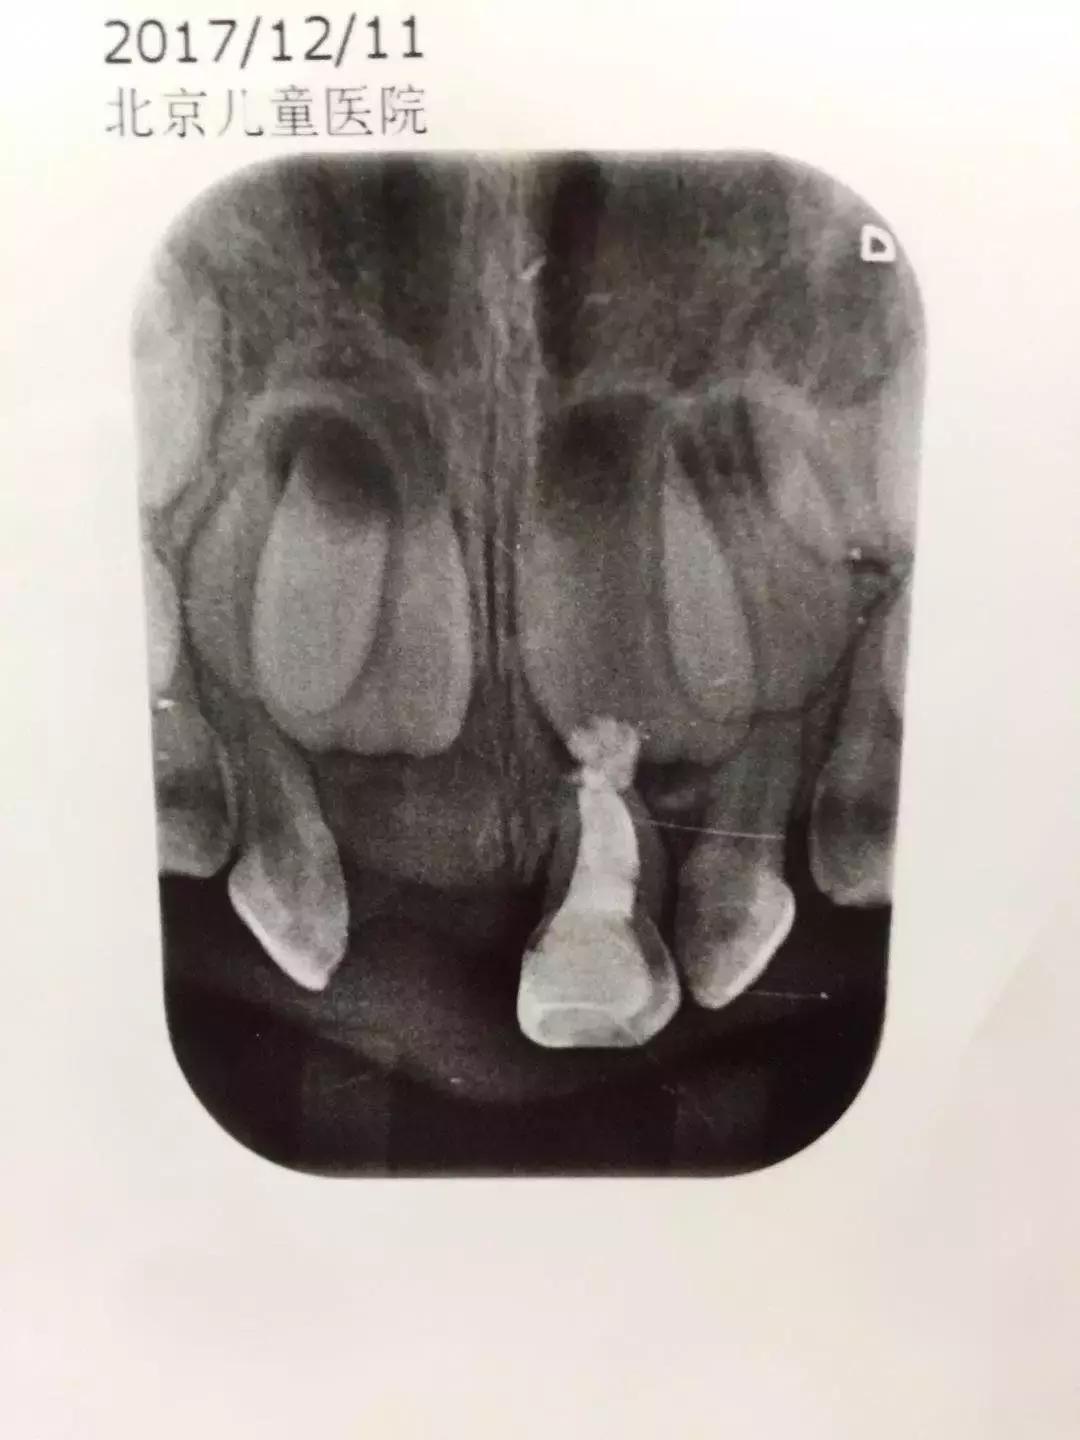

这个是多多的牙片,上面是目前隐藏在牙龈里的恒牙,现在拔了坏掉的龋齿,就等着恒牙萌出来。长出来前娃就要一直是“一颗牙门神”的状态了,心塞

带孩子看牙医怎么不被坑,带孩子看牙花钱